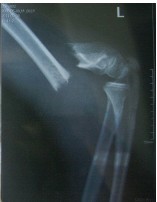

昨日下午,记者在医院见到胡师傅时,他面部还有不少血和尘土。“从刚才的片子看,胡师傅头部有点淤血,右胳膊骨折。伤势不是特别重,但是老人家伤到骨头,比年轻人需要更长时间恢复。”接诊的医生说。